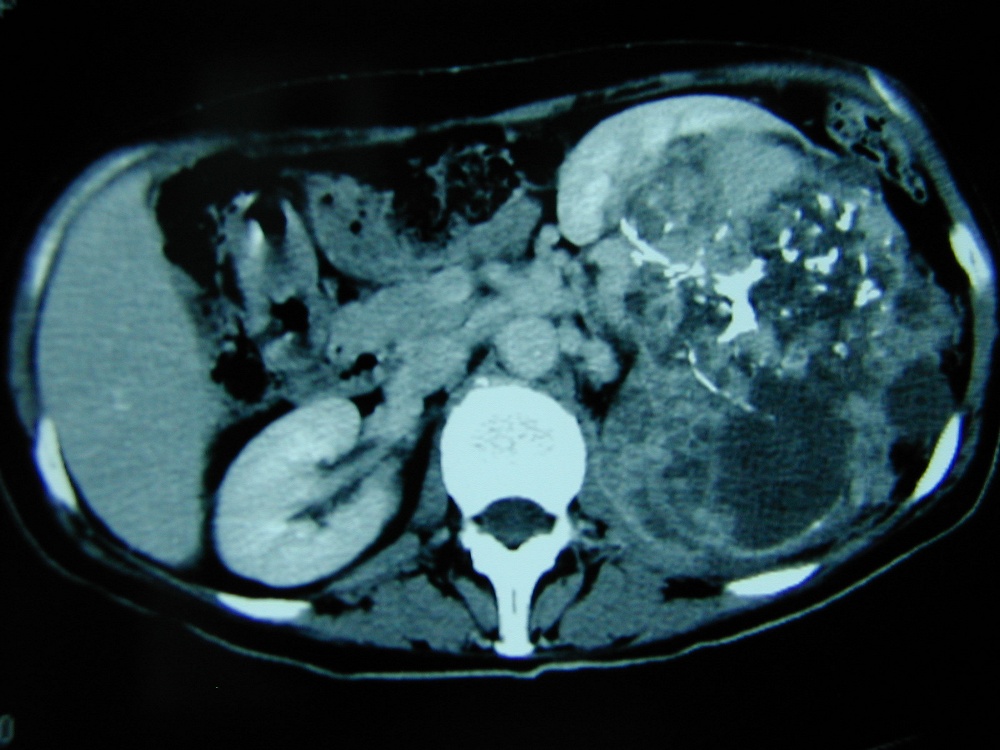

Le Cancer du Rein

Le cancer du rein est une tumeur maligne développée à partir du tissu rénal qui représente 3% de l’ensemble des cancers. Son incidence est en constante augmentation dans les pays industrialisés.

Le diagnostic de cancer du rein est le plus souvent fortuit; parfois, il se révèle suite à des douleurs lombaires ou du sang dans les urines mais ces symptômes, peu spécifiques, se rencontrent aussi dans de nombreuses pathologies bénignes. L’âge moyen au moment du diagnostic est de 62 ans.